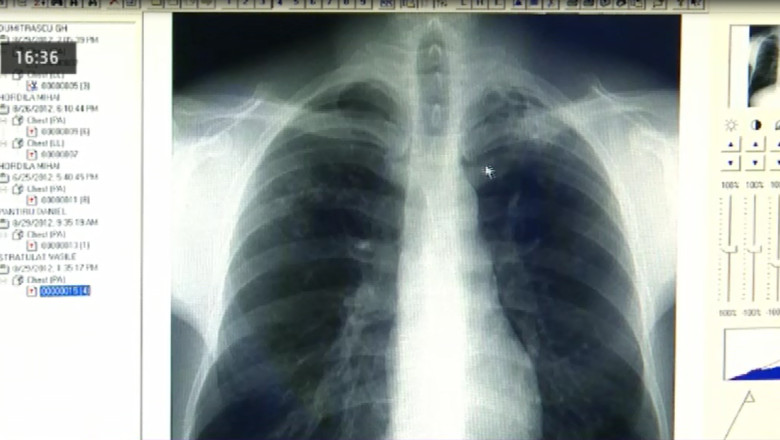

Pacienții ar trebui să meargă la un control la specialist de la primele simptome, spun medicii. Acestea sunt tusea, infecțiile, scăderea în greutate și senzația că rămân fără aer.